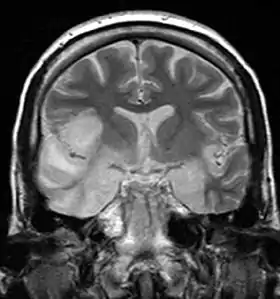

Енцефалі́т (грец. ἐνκεφαλίτις, запалення мозку) — запалення головного мозку (суфікс «іт» саме вказує на запальний характер захворювання). Термін «енцефалопатія» свідчить про відсутність запалення, а процес ураження спричинений переважно судинними порушеннями. Є часто клінічним синдромом багатьох хвороб.